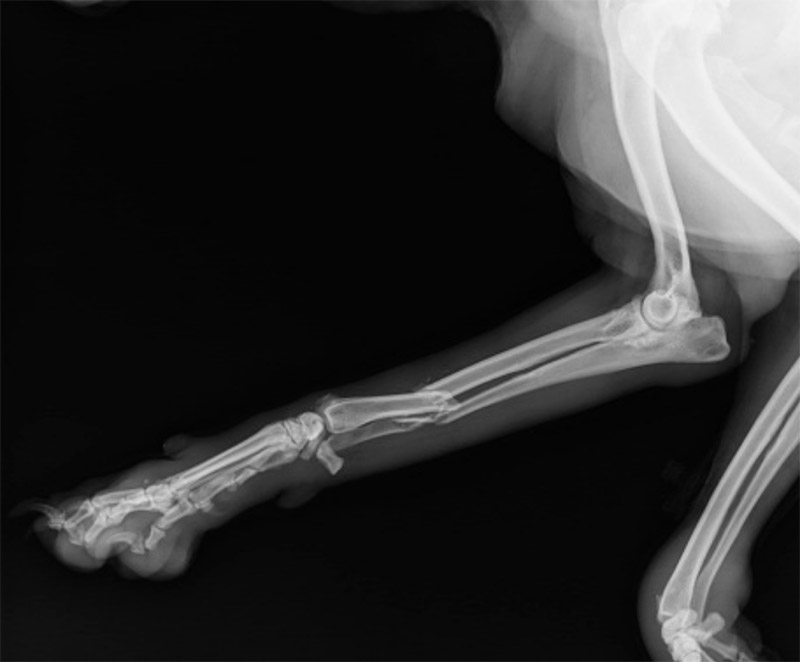

2レントゲン検査(X線撮影)またはCT検査

レントゲンでは、骨折の場所・形・ずれ具合を確認します。必要に応じて複数方向から撮影します。

外科手術(ピン・プレート・ワイヤー固定など)

骨がずれている、関節に近い、複雑な骨折の場合

骨折タイプ・動物の大きさなどにより、様々なピン・プレート・スクリューなどを組み合わせて手術を行います。